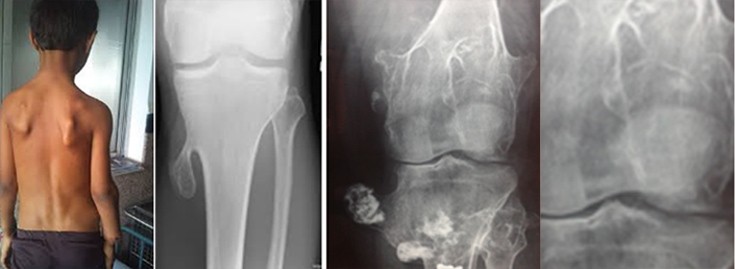

Η πάθηση έχει την ονομασία «πολλαπλές εξοστώσεις» γιατί συνήθως προσβάλλουν τα μακρά οστά και των άνω και των κάτω άκρων.

Οι εξοστώσεις των μακρών οστών ανευρίσκονται είτε τυχαία σε ακτινογραφία ρουτίνας ή είναι τόσο έκδηλα ψηλαφητές, ώστε ο ασθενής αναζητά εξήγηση για τον ψηλαφητό «όγκο» που νοιώθει στο γόνατό του.

Οι εξοστώσεις των μακρών οστών είναι συνήθως καλοήθεις διογκώσεις στο άκρο των μακρών οστών (βραχιονίου-κνήμης-πλευρών) οφειλόμενες στην ετερότοπη εγκατάσταση οστικών κυττάρων στην περίοδο της ανάπτυξης, συγχρόνως με την ανάπτυξη του γενικού σκελετικού χόνδρου. Γι’ αυτό και γίνονται συνήθως αντιληπτές στην εφηβεία.gon2

Στην ψηλάφηση στο ένα ή και στα δύο πόδια, ψηλαφείται συνήθως στην έσω πλευρά του γόνατος μία σκληρή διόγκωση, που υπεγείρει το δέρμα. Δεν είναι επώδυνη στην ψηλάφηση ή την πίεση.

Αναδεικνύεται ευκρινώς στην απλή ακτινογραφία.